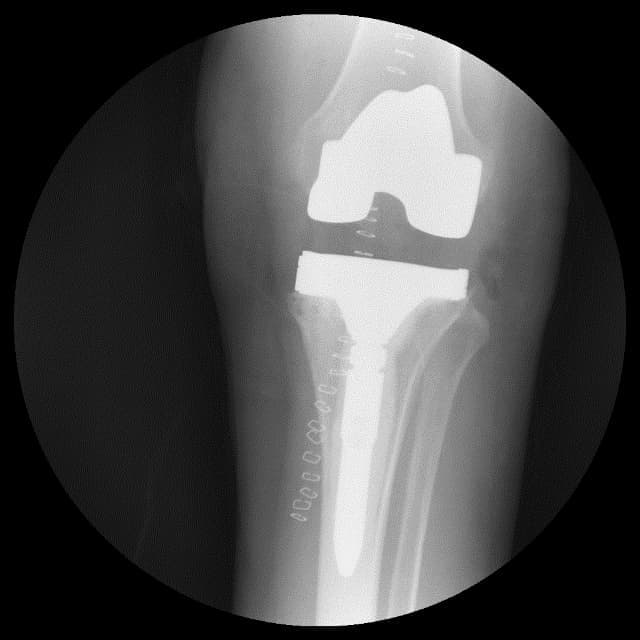

Үе дайрсан ясны анхдагч хавдар, ясны дутмагшлын үед хийгдэх мэс засалimg17Үе дайрсан ясны анхдагч хавдар, ясны дутмагшлын үед хийгдэх мэс засалimg18

Зураг 1. Сэргээн засах мэс заслын өмнөх рентген зураг. Эгц урд, хажуугаас авсан байдал.